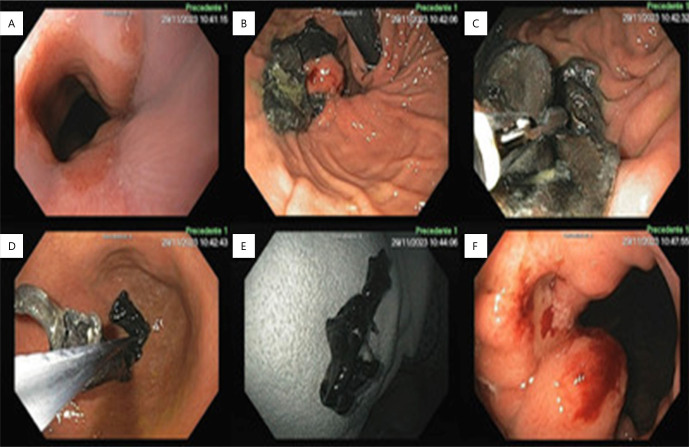

背景:补片在大裂孔疝修补中的应用仍存在争议。与使用补片有关的最可怕的不良事件之一是食管和胃壁的侵蚀。目的:记录裂孔疝手术治疗后胃腔内移位补片的内镜处理。方法:技术方案为等待补片逐步向胃腔内移动,在上消化道内镜下监测,在异物钳辅助下,在最佳时机牵引取出。结果:补片完全取出,进展满意,无并发症。结论:对于无症状且无并发症迹象的补片入胃患者,在补片未粘附胃壁的情况下,可以成功进行内镜监测和随后的异物取出,避免了高发病率和死亡率的手术。

Aims: To record the endoscopic treatment of mesh that has migrated into the gastric lumen after surgical treatment of hiatal hernia.

Methods: The technical option was to wait for the progressive migration of the mesh into the gastric lumen, monitoring with upper digestive endoscopy, with removal by traction at the best time, with the aid of foreign body forceps.

Results: The mesh was completely removed, and the evolution was satisfactory, without complications.

Conclusions: In patients with mesh migration into the stomach who are oligosymptomatic and do not show signs of complications, endoscopic surveillance and subsequent removal of the foreign body can be successfully performed when the mesh is not adhered to the gastric wall, avoiding surgical procedures with high morbidity and mortality.